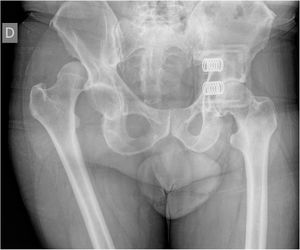

A systematic review by Saulnier et al.12 in 2017 found that very few studies had investigated injuries caused specifically by floods, however it is known that injuries such as sprains (14.4%), non-specific pain (5.6%) and dislocations (2.4%) require conservative treatment in almost all cases. In our population, there was only one case of native posterior dislocation of the hip, with a 48-h evolution, which required closed reduction under sedation in the operating theatre (Fig. 5).